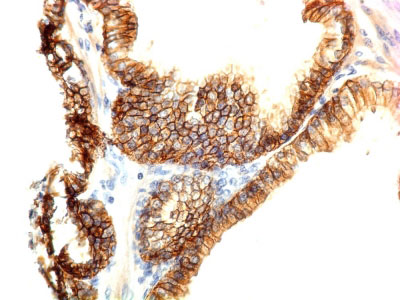

Formalin-fixed, paraffin-embedded human Skin stained with E-Cadherin Monoclonal Antibody (CDH1/1122).

Formalin-fixed, paraffin-embedded human Colon Carcinoma stained with E-Cadherin Monoclonal Antibody (CDH1/1122).